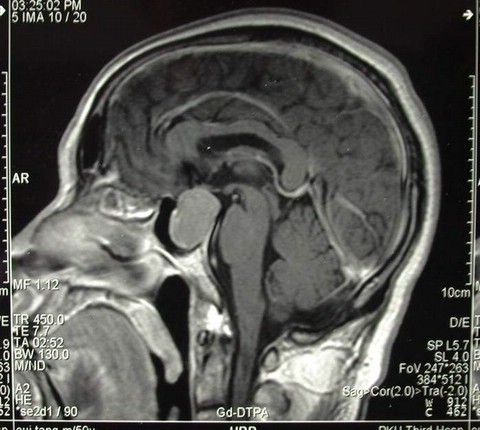

男性,60岁,主因双眼视力下降2个月入院,查MRI示:鞍区巨大占位。

诊断考虑垂体腺瘤。行经鼻蝶手术,全切肿瘤,术后复查如下: